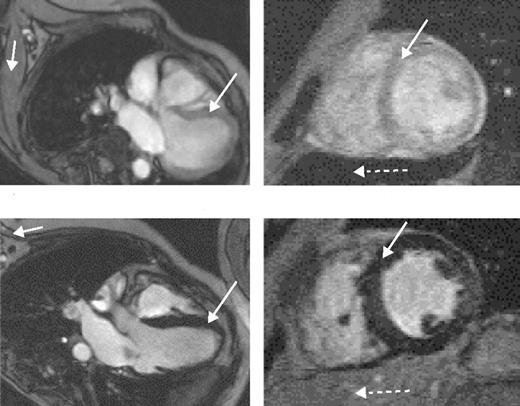

The value of liver iron, whether > 15 mg/g or in the range of 7 to 15 mg/g, as a predictor of cardiac iron has recently been questioned. MRI data using the T2* technique (Figure 5 )9 and spin-echo10 have shown no correlation between cardiac and liver iron, although other MRI techniques, possibly less sensitive and accurate, have shown such a correlation. Possible explanations for these discrepant observations have been discussed.3,9

Cardiac iron

Direct measurement of cardiac iron by endomyocardial biopsy of the right atrium is inappropriate since iron locates mainly to the myocardium of the ventricles. The recent development of a reproducible, sensitive, and accurate indirect measure of cardiac iron using the MRI T2* technique11 has provided substantial important new data. A T2* value less than 20 ms has been found to correlate with the presence of cardiac dysfunction, detected by echocardiography, 24-hour monitoring, or the need for cardiac therapy. It is also valuable for monitoring changes in cardiac iron during intensive chelation therapy.12

The most important aspect of iron chelation therapy is protection of the heart. Two recent studies, albeit retrospective, show significant benefit for the patients receiving deferiprone compared with DFO. In a London study, 15 TM patients who had received deferiprone 75 mg/kg/d for 3 years showed a lower incidence of cardiac disease (assessed by echocardiography and need for cardiac drug therapy) and lower cardiac iron estimated indirectly by MRI T2* than 30 age- and sex-matched patients who had received DFO 40 mg/kg/d subcutaneously on 5–7 days each week (median myocardial T2* 34.0 vs 11.4 ms, P = .02).9 Excess myocardial iron (T2* < 20 ms) was significantly less common in the deferiprone group (27%) than in the DFO group (67%), P = .025.